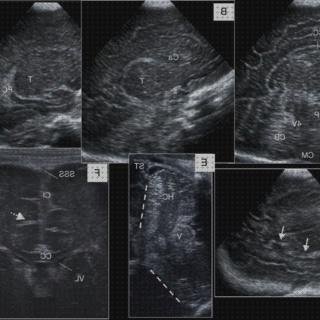

Lactante de 4 meses remitido con datos clínicos de signo febril de treinta y seis horas de variación, abombamiento de fontanela, acidez y rechace de las tomas. De hecho anunciaba lesiones papuloeritematosas y petequiales en integrantes inferiores. En matemáticas leucocitosis con neutrofilia y pcr de 311.83 mg/l. Se hizo ecografía cerebral, entrando a través de fontanela anterior con tubo recto de mayor frecuencia, donde los hallazgos (figura 1) han sido enormemente sugestivos de proceso meníngeo. Posteriormente se procedió a la extracción de líquido cefalorraquídeo (lcr), cuyo análisis bioquímico terminó siendo acorde con proceso contagioso. En la cría de lcr se cortó neisseria meningitidis asegurando la propia diagnosis.

La ecografía transfontanelar juega un papel fundamental en el evaluación inicial de los neonatos y lactantes con temor de meningitis bacteriana, así como en la monitorización de las complicaciones derivadas de esta enfermedad. Las alteraciones ecográficas están presentes entre el sesenta y cinco% y el cien% de los niños con meningitis aguda bacteriana. Los signos precoces son: Aumento del ecogenicidad de los surcos cerebrales, engrosamiento meníngeo (